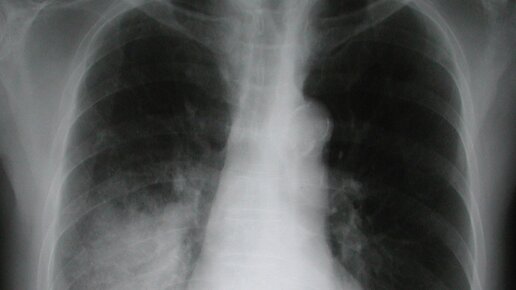

Воспаление легких или пневмония – это серьезное заболевание, которое без правильного лечения может привести к тяжелым последствиям. Однако его не всегда легко распознать: симптомы могут напоминать обычную простуду или бронхит. О том, как понять, что у тебя воспаление легких, а также как отличить пневмонию от других болезней, выяснила Общественная служба новостей. Воспаление легких – коварная болезнь, которую нельзя игнорировать. Если у вас долго держится температура, мучает кашель с мокротой и боль в груди – не занимайтесь самолечением, обратитесь к врачу...

Воспаление легких (пневмония) — инфекционное заболевание легких, возникающее и как самостоятельная болезнь, и как осложнение других заболеваний. Причины заболевания. Пневмония вызывается различными типами микробов, такими как стрептококк, стафилококк и пневмококк, а также некоторыми другими вирусами. Причинами пневмонии могут быть грибковая инфекция, глисты, попадание инородных предметов вдыхательные пути, раздражающая пыль и вредные газы. Непосредственная причина появления пневмонии — это отравление организма токсинами и шлаками, особенно теми, которые находятся в легких и дыхательных путях...